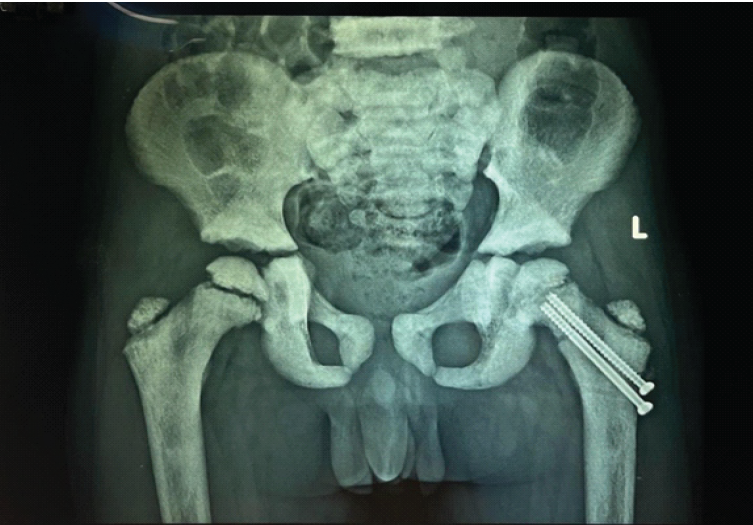

The patient underwent closed reduction on a fracture table using traction and internal rotation, followed by internal fixation with two 4-mm cannulated cancellous screws, deliberately stopping short of the physis (Fig. 2).

Figure 2: Immediate post-operative radiograph showing fixation with two cannulated cancellous screws (May 07, 2024).